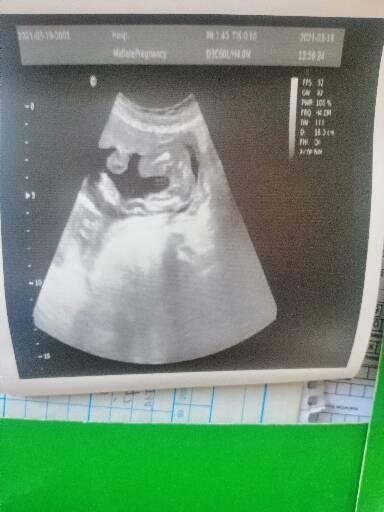

Какво представлява измерването на дължината на шийката на матката по време на бременност и какви са нормалните стойности?

Явно се повдигат органи ли...не знам вече. Дали е нормално?